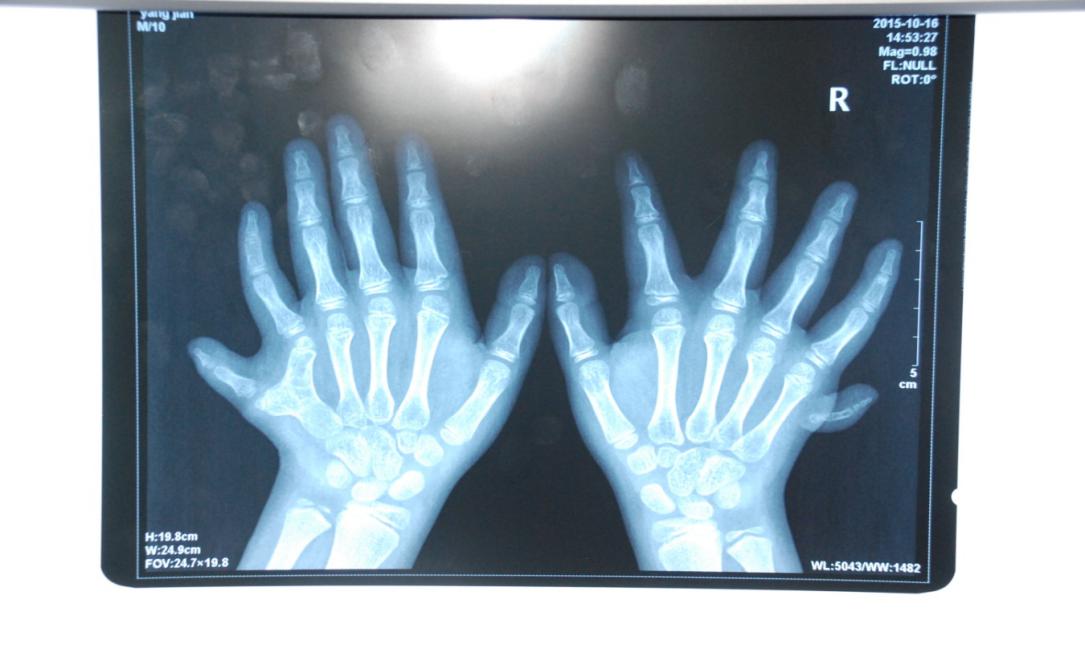

廈門眼科中心小兒眼科修陽暉博士在日常的診療過程中就接診了不少這樣的的特殊家庭,讓其尤為印象深刻的就是一年前接診的BBS綜合征患者。當時來院就診的是一對親兄弟,之前已在多家醫(yī)院做過檢查,因其均有較大散光和斜視,肉眼下眼底檢查未見異常,故外院均診斷為弱視,這也符合眼科門診常規(guī)的診斷邏輯與思維。但由于兄弟倆均有智力發(fā)育遲緩、特殊面容及四肢均有六指和六趾的特異體征引起了修陽暉博士的警覺:會不會是一種特殊遺傳性疾病或綜合征?后續(xù)的檢查結(jié)果進一步證實了修陽暉博士的懷疑---患兒均有夜盲,ERG、VEP及OCT檢查顯示雙眼的視網(wǎng)膜神經(jīng)上皮層結(jié)構(gòu)及功能均明顯異常。由于之前未遇到此種病例,修陽暉博士在診斷一欄寫下視網(wǎng)膜色素變性并打上了個問號,同時留下了病人的聯(lián)系方式。

BBS綜合征(Bardet-Biedl綜合征)是一種主要累及纖毛結(jié)構(gòu)與功能的罕見常染色體隱性遺傳性疾病。纖毛分布于哺乳動物體內(nèi)的大多數(shù)細胞,它是一種廣泛存在于各種細胞表面的細胞器,體型微小但結(jié)構(gòu)復雜、作用強大,能感知細胞外機械和化學信號變化并協(xié)助其轉(zhuǎn)導到細胞內(nèi)部從而引起細胞應答。高等動物的視覺、觸覺、嗅覺、聽覺的傳遞都依賴于體內(nèi)外正常的纖毛結(jié)構(gòu)和功能。因此BBS綜合征常累及全身多個系統(tǒng)和器官,在臨床上主要表現(xiàn)為:視網(wǎng)膜色素變性、智力發(fā)育異常、向心性肥胖、多指(趾)、性腺發(fā)育異常、腎臟異常。除此之外還有許多諸如:語言發(fā)育障礙、聽力異常、嗅覺異常、斜視、白內(nèi)障、散光、牙齒發(fā)育異常、短指(趾)、并指(趾)、肝纖維化、糖尿病、高血壓等表現(xiàn)。